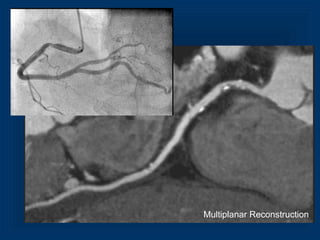

MPR of LAD in Cross SectionThin MIP

Detection of Plaque

Sensitivity 82%, Specificity 88%

Achenbach et al. Circulation 2004

MPR of LADin Cross SectionThin MIP Detection of Plaque Sensitivity 82%, Specificity 88% Achenbach et al. Circulation 2004